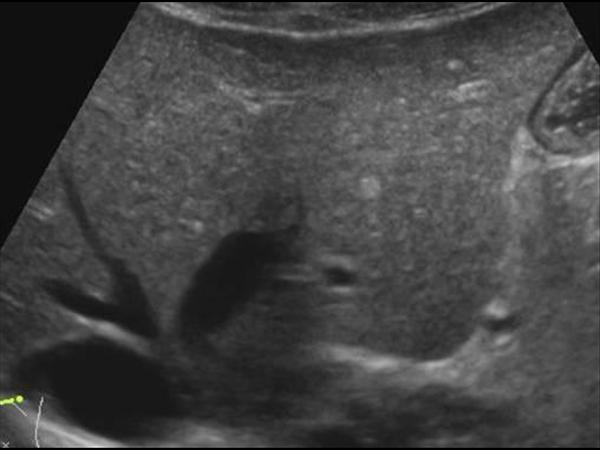

Gan nhiễm mỡ

» Thông tin: Nữ giới – 56 tuổi.

» Lâm sàng: Kiểm tra sức khỏe.